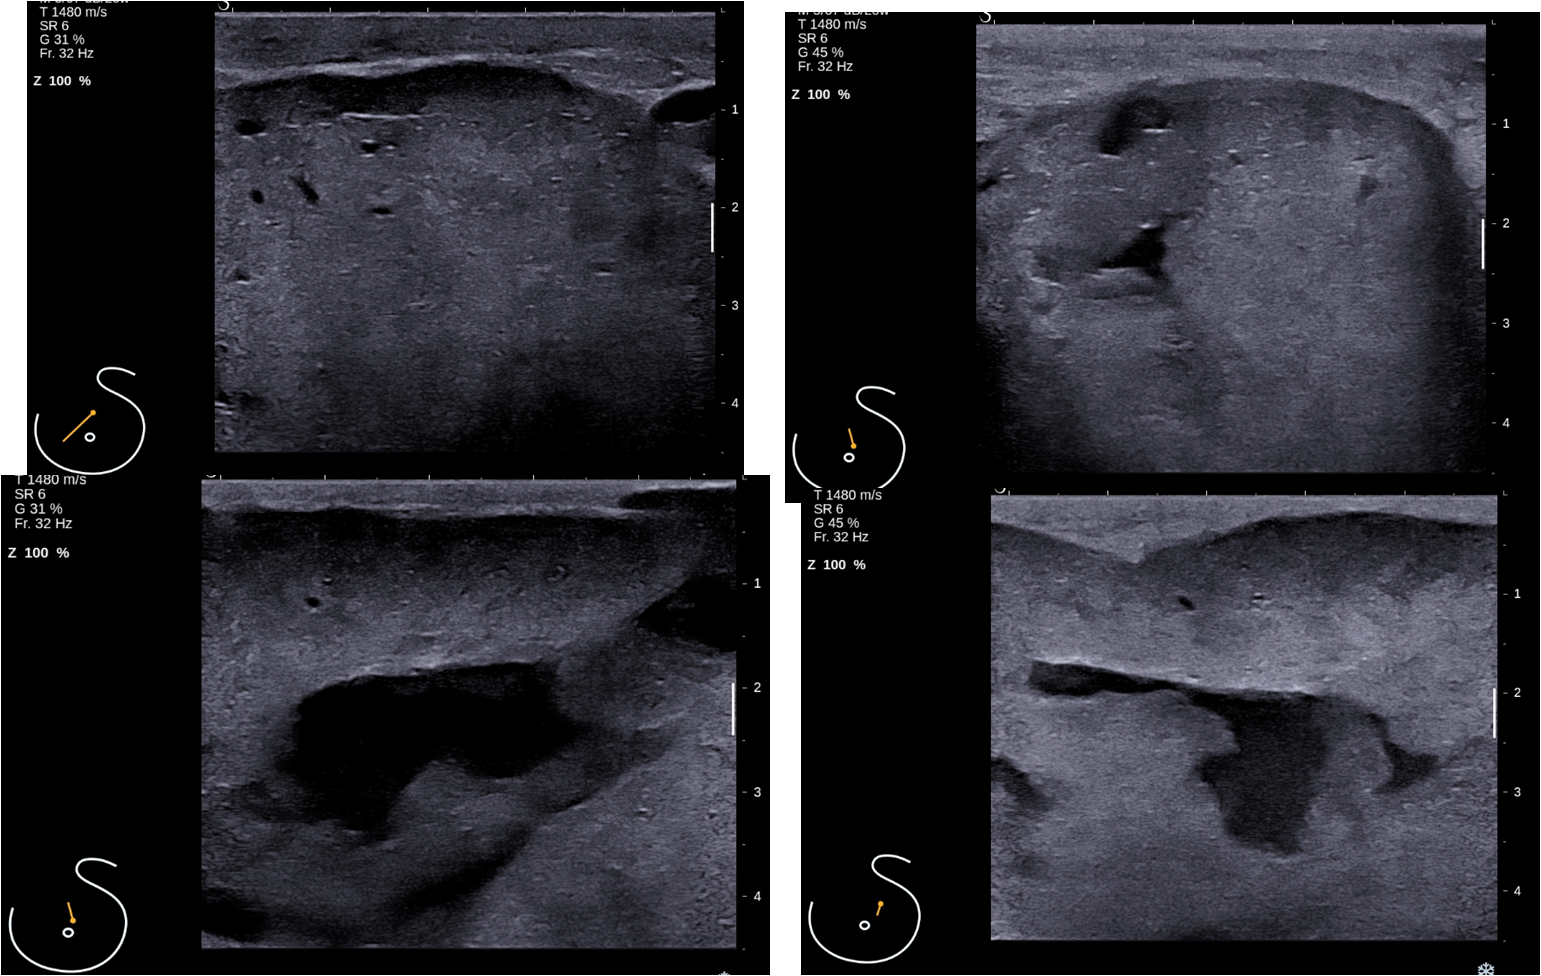

The left breast is enlarged and shows a large circumscribed mass of density similar to the fibroglandular parenchyma, occupying nearly entire left breast. There are no calcifications associated with the mass, however there is mild trabecular thickening and nipple retraction. The left breast mass is circumscribed , round to oval, mildly hypoechoic in appearance and shows multiple irregular fluid clefts (arrow). Excision specimen histology: Spindle cell tumour with infiltrative borders, increased stromal cellularity and moderate nuclear atypia. Areas of necrosis present. Mitotic count 5/10 HPF - Overall features are those of borderline phyllodes tumour